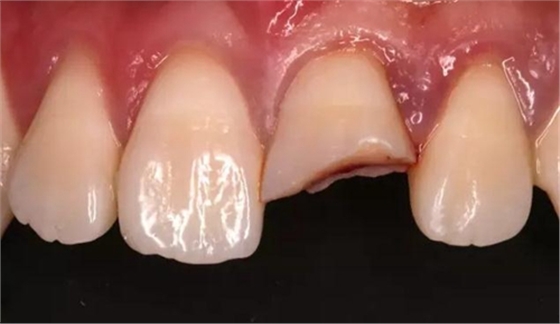

口內檢查:21切1/3-1/2折斷,髓腔暴露,探痛明顯

近中鄰面探及齲損,松-,叩+,齦緣輕度紅腫,探及齦下結石。

術前口內照

斷冠

折斷之牙體嚴重脫水,呈白堊色,斷端對位后吻合度較好,僅少許牙體缺損。